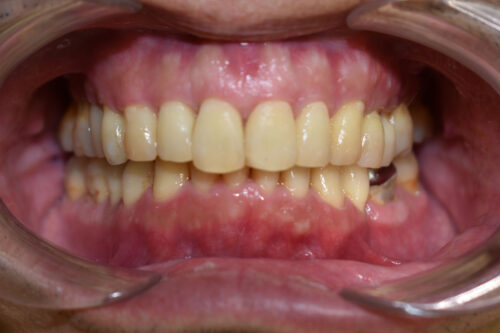

ワイヤー9か月後です。

ワイヤー期間 9か月, 14回来院

また、下顎の欠損部分は

全てスペースを閉じて

ご自身の歯で

かめるように

矯正治療を終えました。